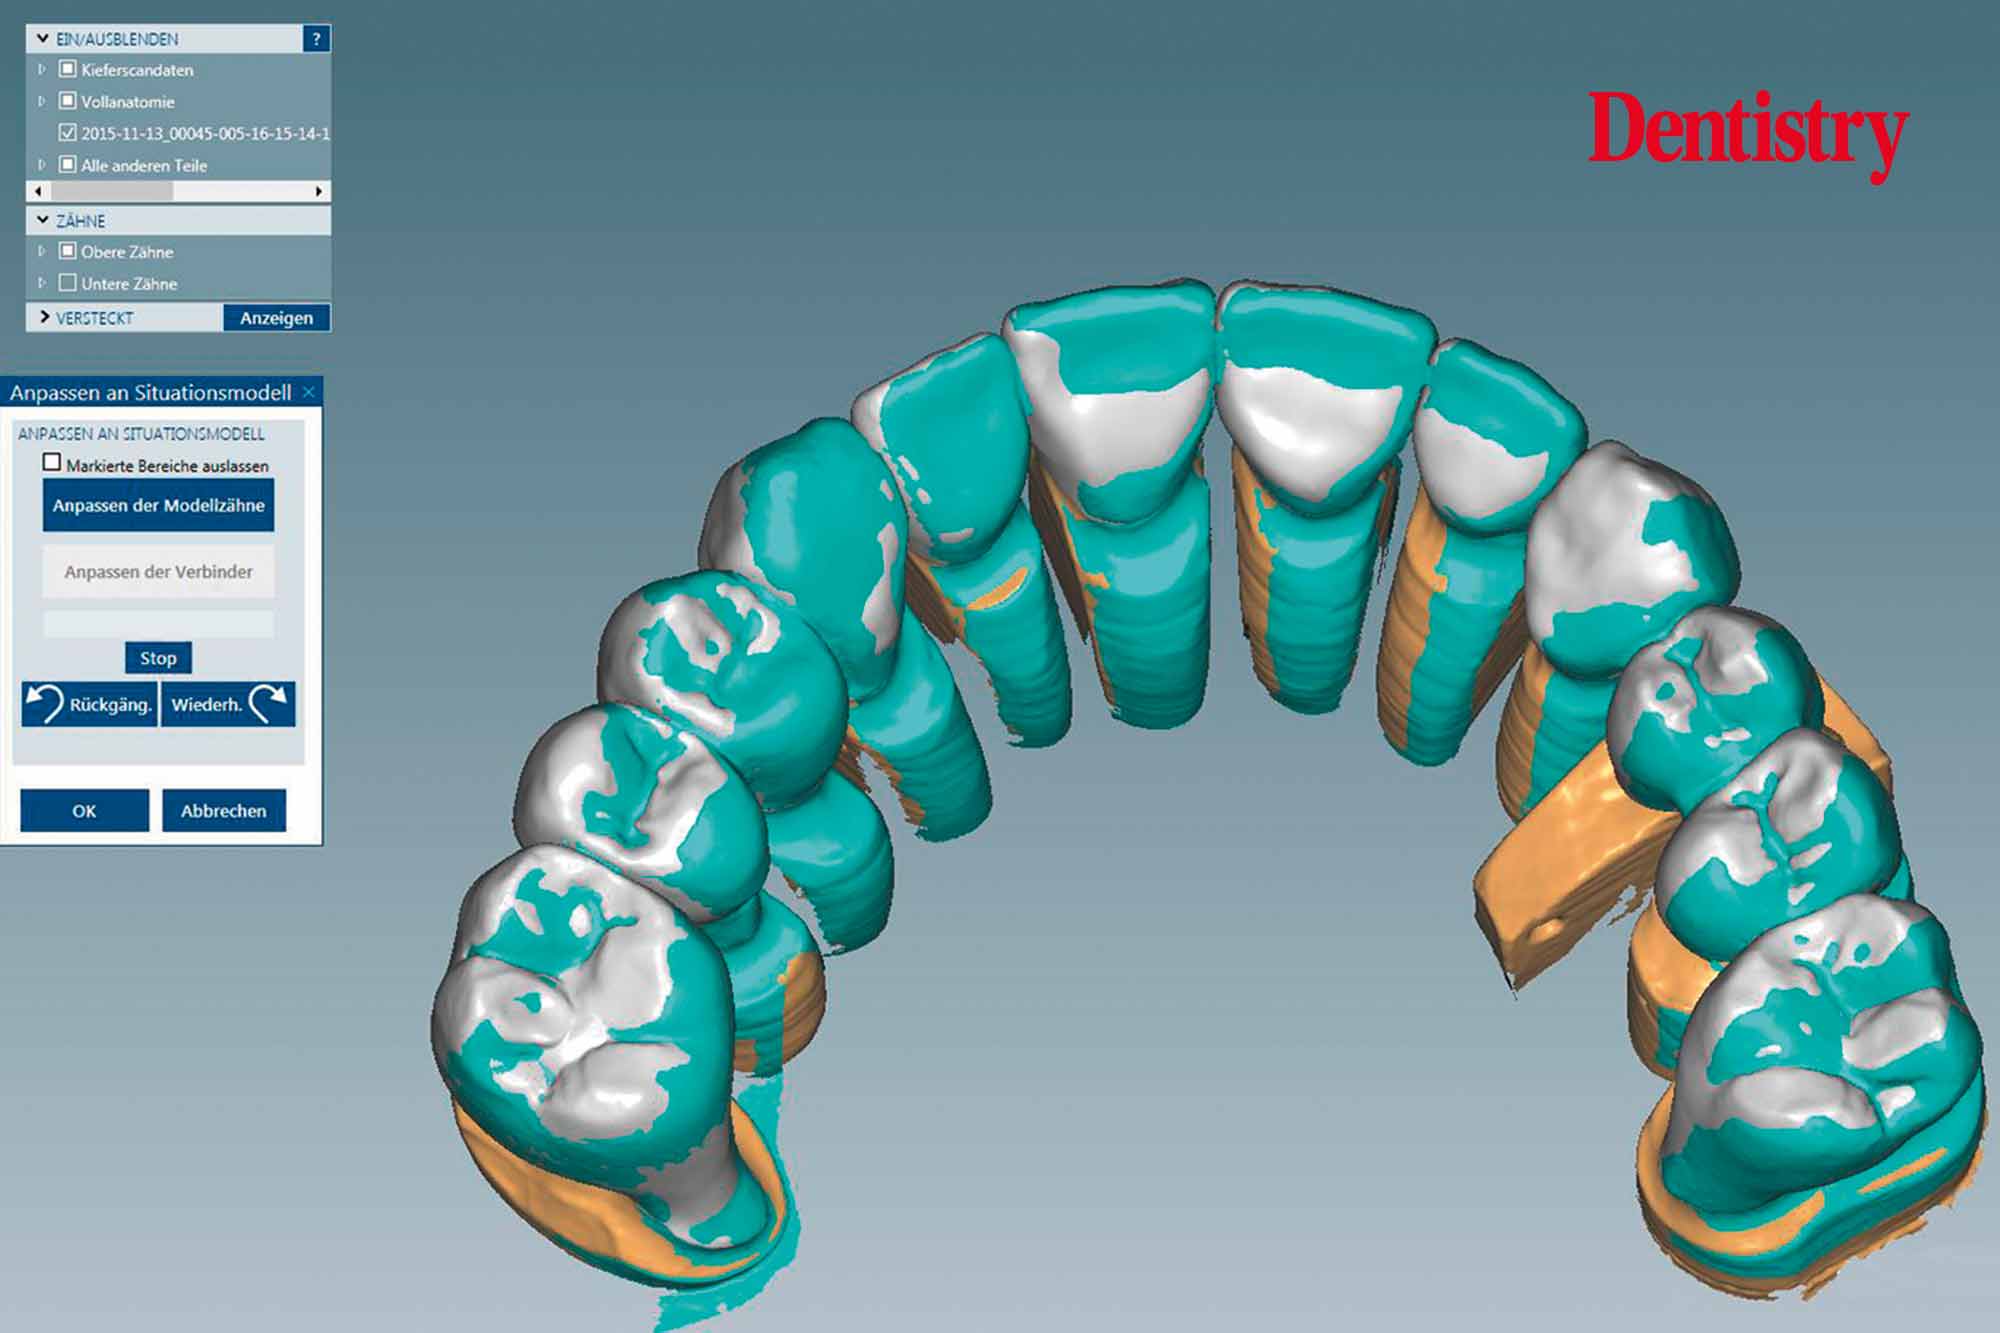

CAD design of the final crowns

Using the CAD software (Figure 12), we were able to round off and refine the areas on the temporary crowns that had been ground and modified intraorally. As a result, this left the remaining areas unchanged.

Figure 13 shows the areas that were adjusted intraorally in green and the remaining unchanged areas in blue. The plan was to fabricate Ceramill Zolid FX crowns on the maxillary teeth first. This is so subsequent corrections on the lower temporary crowns would mean that less corrections would be necessary for the final lower crowns.